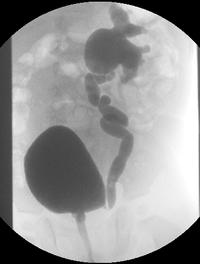

Les coliques néphrétiques (CN) sont l'une des urgences les plus fréquentes dans le monde puisque, par exemple, on estime que, chaque [...]

Bien que le caractère familial du reflux vésico-urétéral [RVU] soit établi, l’exploration de la fratrie d’un enfant porteur d’un RVU [...]

A l’âge de 7 ans, 2 % des garçons et 8 % des filles ont présenté une infection urinaire (IU). Ces épisodes sont favorisés par des reflux [...]